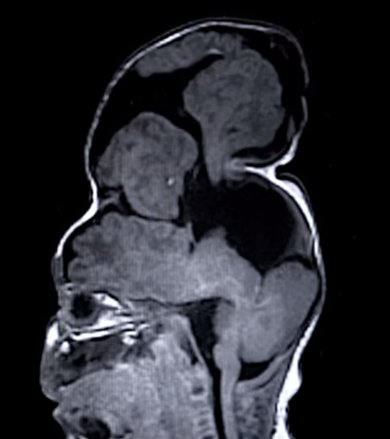

این کودک که بنتلی نام دارد مبتلا به یک بیماری نادر به نام آنسفالوسل یا بیفیدوباکتریوم جمجمه بود که مشکلش در هفته 22 بارداری مادر و با انجام سونوگرافی تشخیص داده شد.

پزشکان کلینیک کلیولند اوهایو طی انجام یک عمل جراحی فوق العاده دشوار و خطرناک موفق شدند مغز یک کودک را که در خارج از جمجمه شکل گرفته بود به حالت طبیعی برگردانند.

انسفالوسل (encephalocele) نوعی بیماری مادرزادی است که به سبب تشکیل ناقص سلول‌های عصبی جنین بروز می‌کند.

در این بیماری بخش‌هایی از مغز به صورت برآمدگی، از طریق روزنه‌های جمجمه بیرون زده و پوست و یا غشاء نازکی روی آن را می‌پوشاند.

پزشکان برای انجام این عمل جراحی از مدل‌های چاپ سه بعدی استفاده کردند. 100 سانتی متر مکعب از مغز بنتلی خارج از جمجمه وی شکل گرفته بود، به طوری که جراحان ناچار به گسترش جمجمه او شدند. آنها قبل از انجام این عمل جراحی از یک مدل پلاستیکی استفاده کردند تا نتیجه این عمل را پیش بینی کنند و دریابند که چه میزان از مغز را می‌توان در جمجمه جای داد.